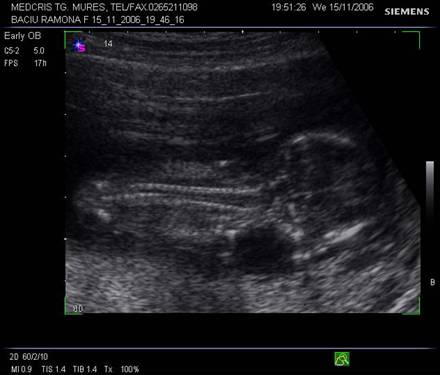

Fig. nr.108. Sarcina 7 saptamani la ecografia abdominala.